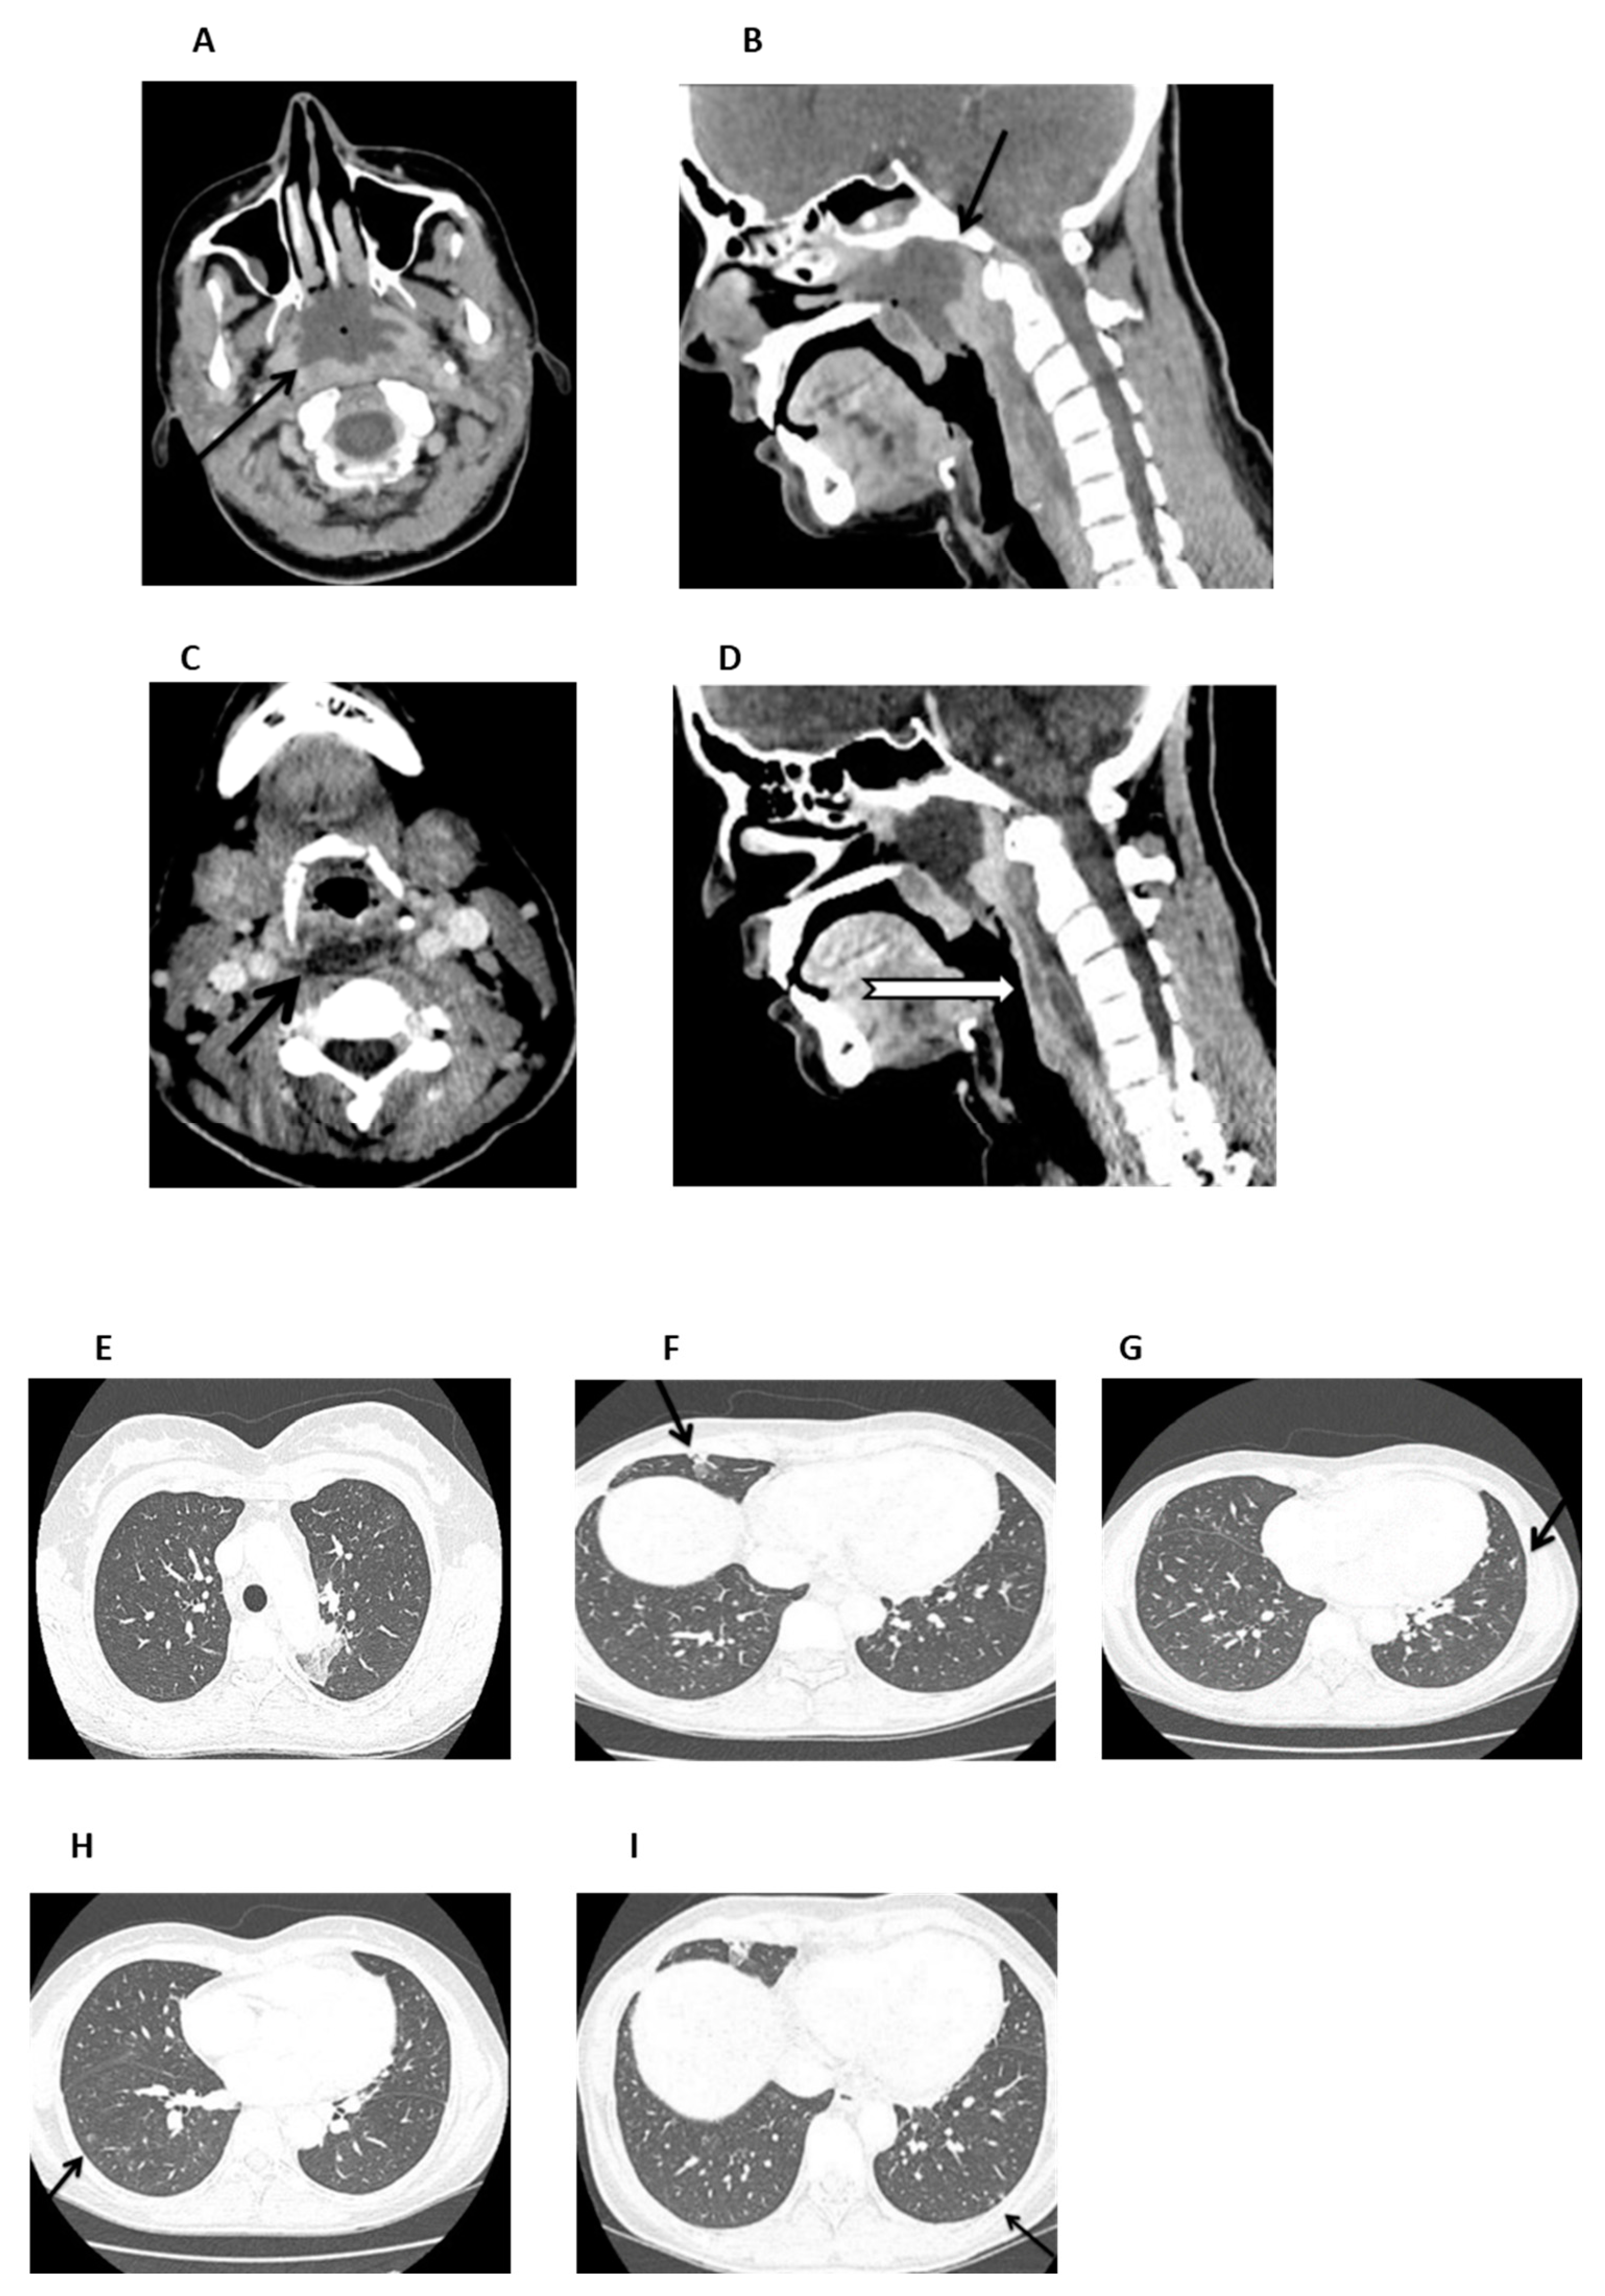

2. Case Presentation